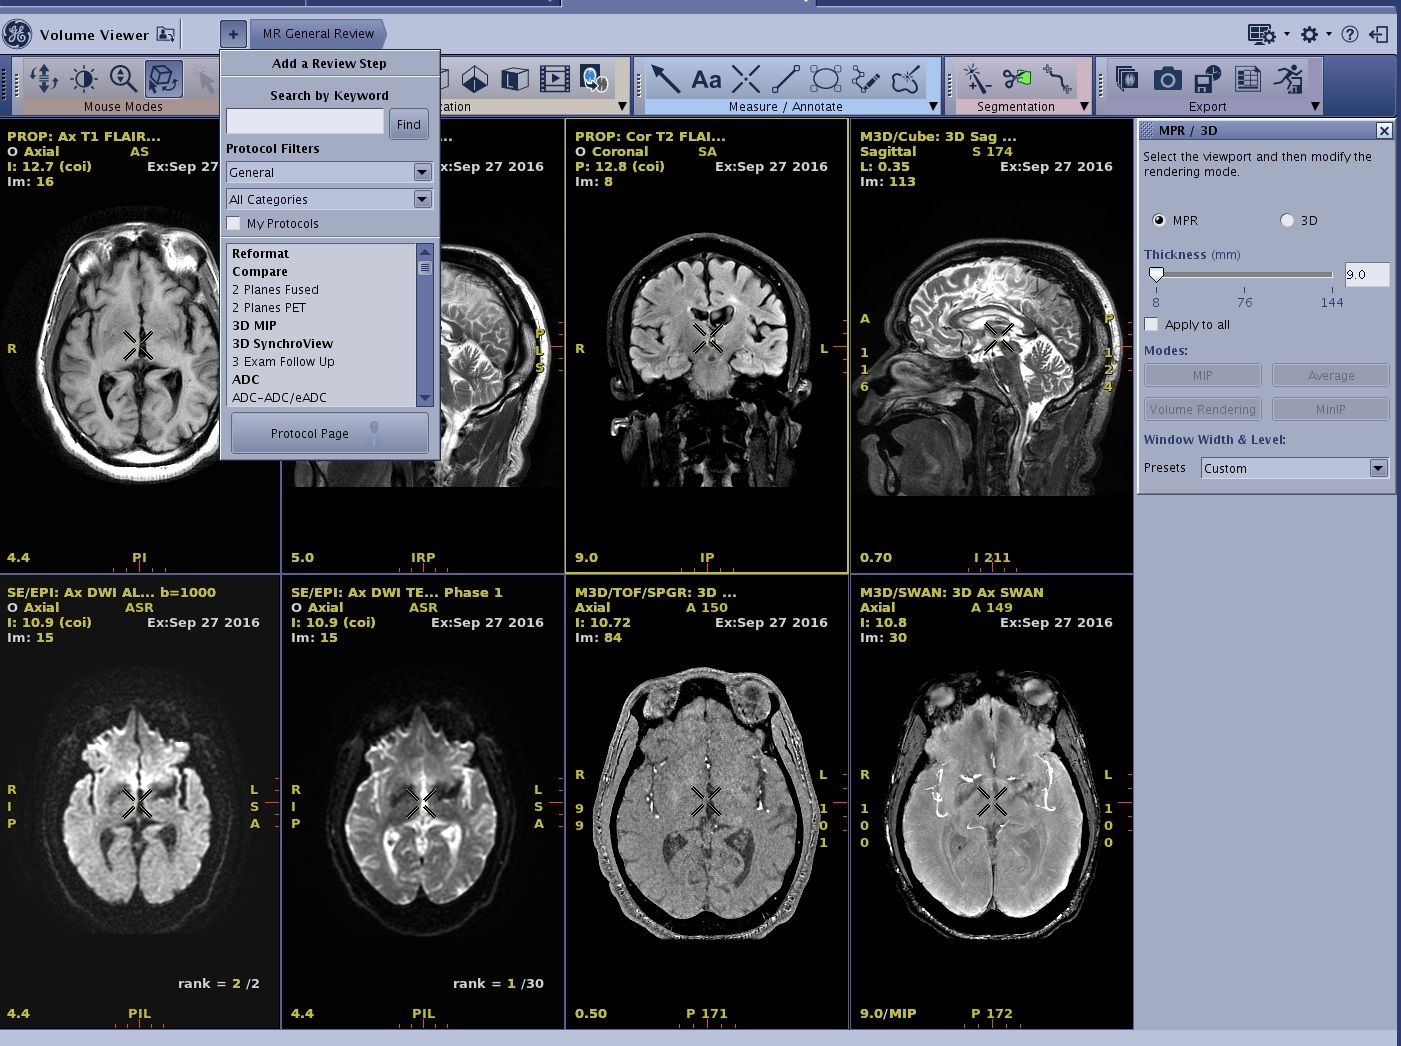

- The application launches with a format based on the number of series selected from the Loading Panel. Each viewport has an image from the selected series. MR General Review is the default Review Step visible.

- In this example, if one of your 8 series is a spectroscopy series it will wrap the first series to the 8th position to create an even format.

Figure 1. Example of 7 series selected from the Loading panel